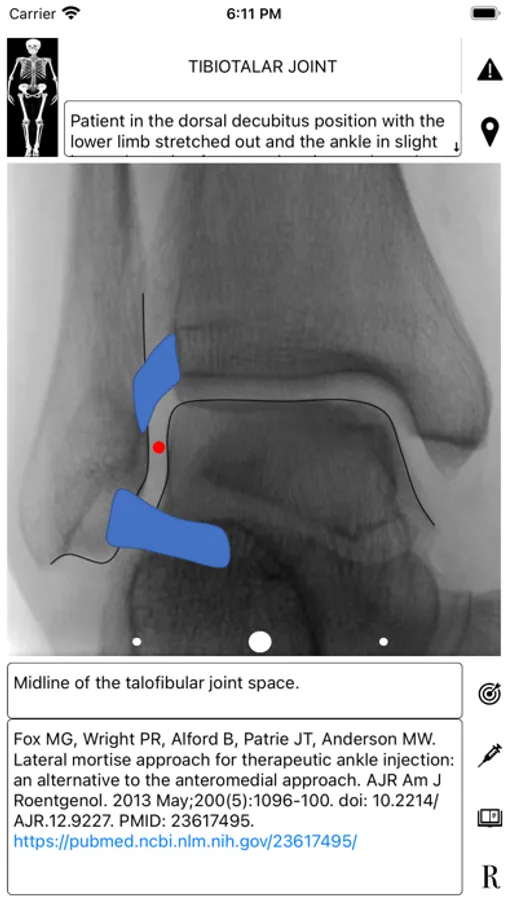

ArthroGuide targets residents, fellows, and physicians who perform fluoroscopically guided arthrograms and pain management injections, including spinal injections. It results from more than 25 years of experience in performing and teaching these procedures.

A visual interface facilitates a quick and efficient review of the information. Find information on patient positioning, puncture site, equipment used, products injected, and the steps to perform therapeutic injections and arthrograms preliminary to an MRI or CT scan. Access relevant references online using hyperlinks directly from within the application. Take advantage of procedural tips, recommendations, and cautionary statements.

ArthroGuide Screenshots